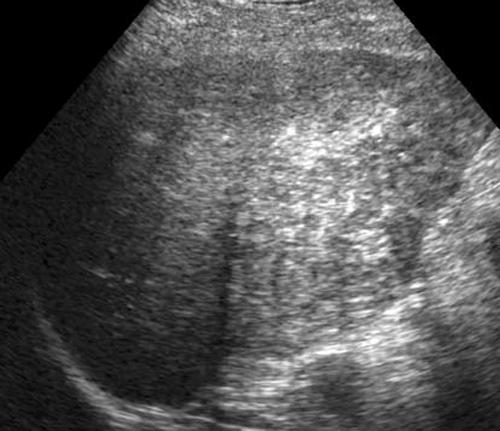

Diffuse Hepatocellular disease

Affects the hepatocytes and interferes with liver function

What is the sonographic appearance of the Diffuse Hepatocellular disease?

Increased echogenicity

Enlargement of affected

area

Decreased penetration

Difficult to identify liver

structures

Presentation: Asymptomatic, jaundice, nausea, vomiting

What is Fatty infiltration?

Fatty liver is an acquired but reversible disorder of metabolism. Fatty filtration implies increased lipid accumulation in the hepatocytes.

What is the sonographic appearance of fatty filtration?

Enlargement

of the lobe.

Difficult to

image

Increased echo texture